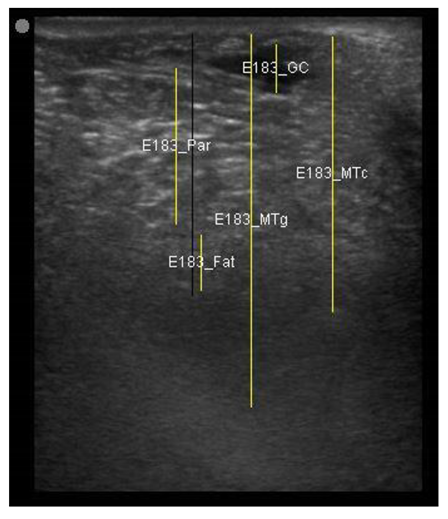

| 109 days of pregnancy (P109) Scanning depth 4.7 cm | ![]() | ![]() | MT generous: 36.8 mm MT conservative: 27.2 mm Gland cistern: 4.7 mm Parenchyma: 15.4 mm Fat Pad: 5.5 mm |